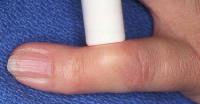

A standard plastic disposable flashlight is fine, but better if the tip is wrapped in opaque electrical tape to limit the light flare through the sides of the flashlight.